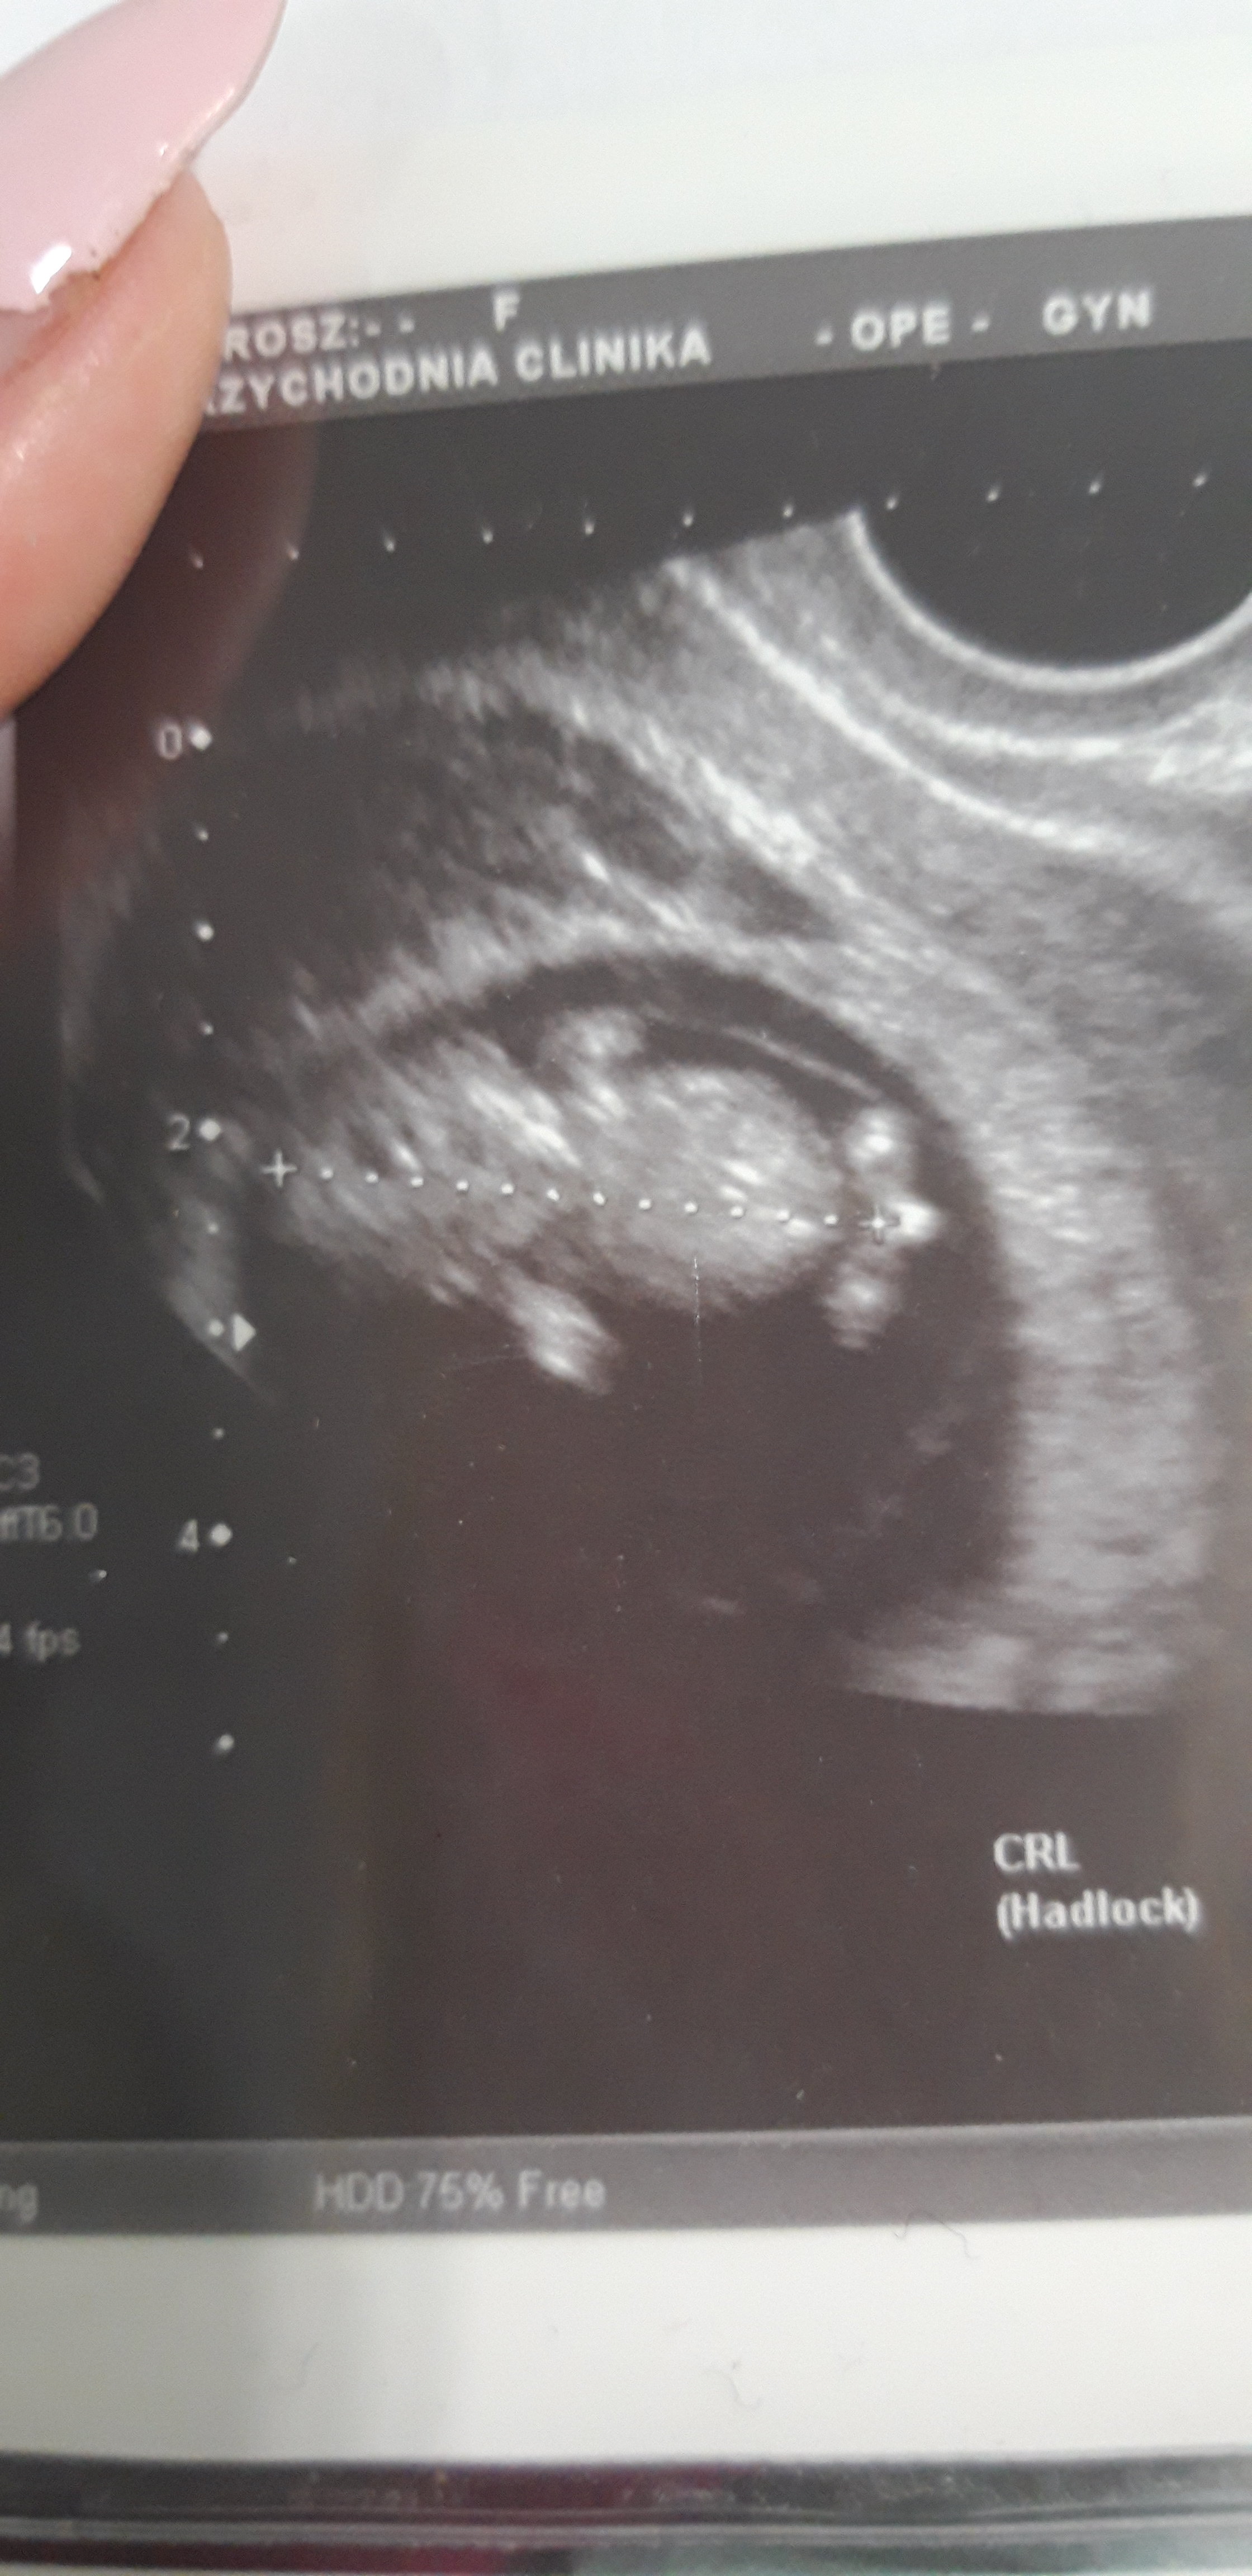

Kochane moje, jestem już po wizycie. Z malenstwem wszystko dobrze. Rosnie jak na drożdżach. Okazalo się po badaniu, że zrobiła mi się nadzerka i stad to krwawienie po aplikacji luteiny. Więc luteina idzie w odstawke i mam brać tylko duphaston. I mala niespodzianka dla mojego partnera: po usg lekarz stwierdzil, ze prawdopodobnie będzie chlopak

Załączniki

• 20190618_120202.jpg